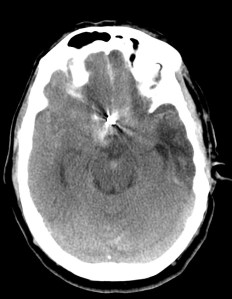

Aunque la RM tiene mayor sensibilidad para el diagnóstico de sangrado, es la TC la prueba de primera línea debido a su mayor disponibilidad. Observaremos la característica imagen de hiperdensidad en las cisternas basales que corresponde a la sangre extravasada. La mayoría de las veces veremos el característico aumento de densidad alrededor del polígono de Willis (65%), que es donde ocurren la mayoría de las roturas de aneurismas, y también en la región de la cisura de Silvio (30%). Podemos ver también sangre en la fosa interpeduncular o asta occipital de los ventrículos laterales.

Hemorragía perimesencefálica – 10%: Es la hemorragia que queda confinada a las cisternas próximas al mesencéfalo y el sangrado central está inmediatamente anterior a dicha estructura, aunque también puede encontrarse signos de sangrado cercanas a protuberancia, cisternas ambiens y cuadrigéminas. No hay extravasación a cisura de silvio ni a la interhemisférica en su porción anterior. Puede haber sedimento de sangre en el asta posterior de los ventrículos laterales pudiendo producir su ensanchamiento.

En 95% pacientes con una hemorragía perimesencefálica no se encuentra punto de sangrado, se piensa que puede ser venoso. Entre el 2 y 5% de los pacientes puede ser causada por una rotura de un aneurisma de la fosa posterior, un angio-TC es conveniente para descartarlo.